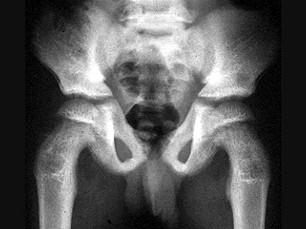

问题 男,6岁,来自干旱地区,腰背疼痛四肢关节酸痛,结合图像,最可能的诊断是?(?)

选项 A.氟骨症 B.畸形性骨炎 C.石骨症 D.髋关节结核 E.甲状旁腺功能亢进

答案 A